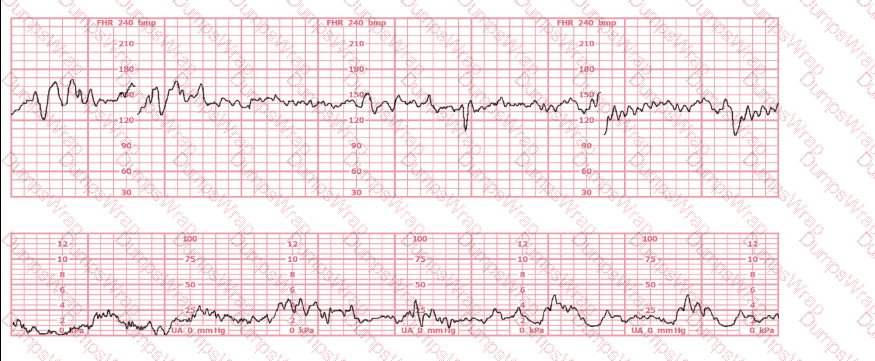

Based on the fetal heart rate tracing shown, the expected fetal pH would be:

Options:

Above 7.15

Below 7.15

Unaffected by the fetal heart rate

Answer:

AExplanation:

Comprehensive and Detailed Explanation From Exact Extract–Based NCC C-EFM References:

Assessment of likely fetal acid–base status is grounded in NCC-aligned principles that correlate fetal pH with fetal heart rate patterns, especially variability, presence/absence of accelerations, and type and depth of decelerations.

This tracing shows the following features:

Baseline:

The fetal heart rate baseline is approximately 140–150 bpm, within the normal 110–160 bpm range.

Variability:

Moderate variability is present—approximately 6–25 bpm amplitude.

Per NCC and NICHD definitions, moderate variability is strongly associated with normal fetal oxygenation and normal fetal pH > 7.20–7.25.

Accelerations:

There are occasional small accelerations, another strong indicator of normal fetal acid–base status.

Decelerations:

The tracing shows occasional variable decelerations, shallow and brief, recovering rapidly, typical of intermittent cord compression.

NCC references emphasize that intermittent, non-recurrent variables with moderate variability do not correlate with acidemia.

Uterine activity:

Contractions are present but not excessive, and fetal response remains reassuring.

Correlating tracing features with fetal pH (per NCC, AWHONN, Simpson, Menihan):

Moderate variability is the strongest intrapartum indicator of normal fetal pH.

The NICHD/NCC consensus repeatedly states that:

“The presence of moderate variability reliably predicts adequate fetal oxygenation and a fetal pH above the threshold associated with metabolic acidemia.”

Fetal pH below 7.15 is associated with:

Absent variability

Recurrent late decelerations

Recurrent deep variable decelerations

Prolonged bradycardia

None are present in this tracing.

Because the tracing demonstrates moderate variability, intermittent uncomplicated variables, and no recurrent late decelerations, the physiologic expectation is that the fetal pH remains normal, significantly above 7.15.

Therefore, the correct answer is: A (above 7.15).